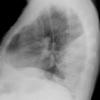

Loc'd fluid Lat